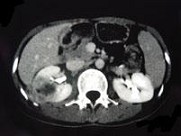

- 多项选择题女,33岁, 右肋腹痛7天,尿检可见大量的脓细胞, CT平扫+增强如图所示,下列说法正确的是 ( )

A、右肾体积增大,其内可见类圆形低密度病灶

B、增强扫描可见该病灶不均匀强化,其内有无强化的坏死灶

C、右肾病灶边界模糊不清

D、考虑为右肾囊肿合并感染

E、考虑为右肾脓肿